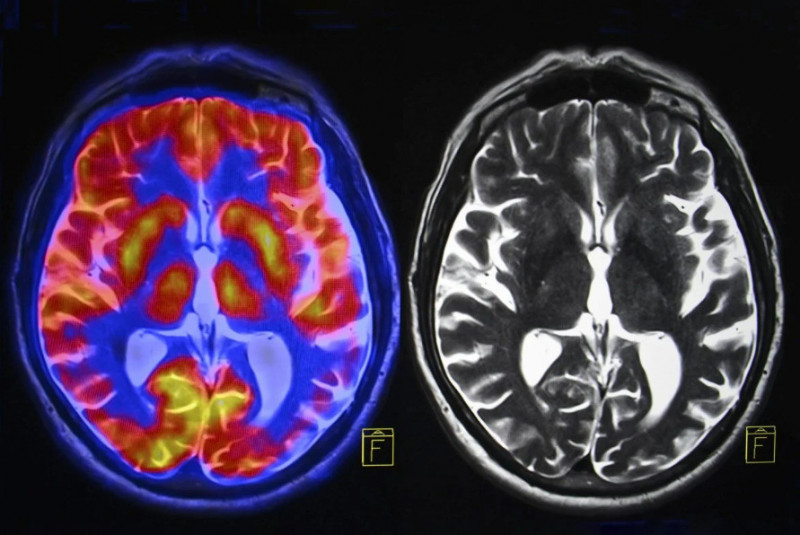

根據科學網站《SciTechDaily》報導,由中國昌平實驗室牽頭,聯合美國聖路易斯華盛頓大學醫學院及其他機構的國際研究團隊,發現1個與巴金森氏症核心症狀相關的軀體認知動作網路(SCAN)。SCAN位於運動皮質(大腦中控制自主運動的區域)內,負責將行動計畫轉化為實際動作,並監控這些動作的執行過程。

為了驗證此想法,研究團隊分析了來自美國和中國800多名參與者的多種腦部影像數據。該研究納入了接受腦深部電刺激(DBS)或非侵入性療法(如經顱磁刺激、聚焦超音波刺激)的巴金森氏症患者。此外研究也納入了健康志願者和其他運動障礙患者作為對照組。

研究發現,巴金森氏症1個顯著特徵是SCAN與皮質下區域(大腦中負責情緒、記憶和運動控制的區域)之間存在異常強的連結。採用的療法若能降低過度連結,就能展現出最佳療效。研究團隊確認,經顱磁刺激療法較有效。用該療法刺激患者SCAN時,症狀改善程度是刺激鄰近腦區的2倍以上。